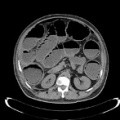

- CT abdomen/pelvis with IV contrast (and PO contrast if possible)

- IV contrast improves soft tissue resolution in the abdomen and pelvis and improves diagnostic accuracy and should be considered even in the presence of acute kidney injury.

- PO contrast improves bowel resolution and the identification of perforation. Presence of PO contrast may help to distinguish intra-abdominal abscesses from adjacent bowel.

Large bowel perforation. Case courtesy of Dr Ian Bickle, <a href="https://radiopaedia.org/">Radiopaedia.org</a>. From the case <a href="https://radiopaedia.org/cases/55375">rID: 55375</a>.